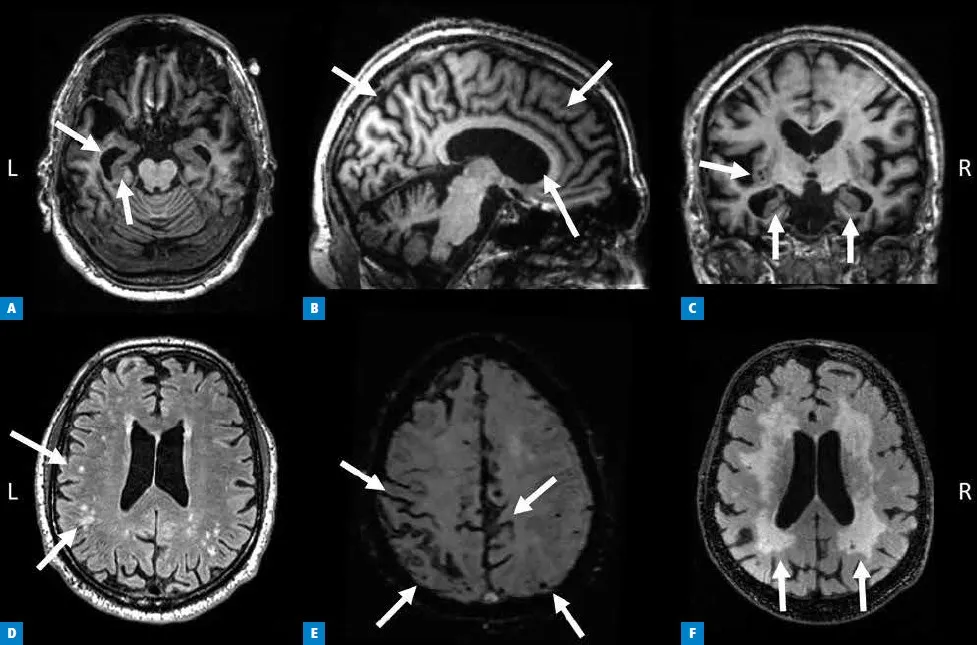

W przeciwieństwie do większości chorób psychicznych, w diagnostyce chorób neurodegeneracyjnych, takich jak choroba Alzheimera czy otępienie czołowo-skroniowe, rezonans magnetyczny odgrywa absolutnie kluczową rolę. MRI pozwala nam uwidocznić tak zwane zaniki korowe (atrofię), czyli zmniejszenie objętości tkanki mózgowej. Ich lokalizacja i nasilenie, widoczne na obrazach MRI, są podstawowym markerem diagnostycznym. Na przykład, w chorobie Alzheimera często obserwujemy zaniki w płatach skroniowych i ciemieniowych, szczególnie w obrębie hipokampu. W otępieniu czołowo-skroniowym zaniki są najbardziej widoczne w płatach czołowych i skroniowych, co doskonale koreluje z objawami klinicznymi.

Dlatego rezonans jest tak ważny w tych przypadkach. Zaburzenia nastroju, zmiany osobowości czy zachowania, a także problemy z pamięcią i koncentracją mogą być pierwszymi, a czasem nawet jedynymi objawami rozpoczynającego się procesu otępiennego. Jest to szczególnie istotne u osób w starszym wieku, gdzie objawy psychiczne mogą być mylnie interpretowane jako "zwykłe" starzenie się lub typowa depresja. MRI pozwala nam odróżnić te stany i wcześnie zdiagnozować chorobę neurodegeneracyjną, co jest niezwykle ważne dla wdrożenia odpowiedniego leczenia i wsparcia.Przyszłość diagnostyki psychiatrycznej: czy zaawansowane techniki MRI zmienią zasady gry?